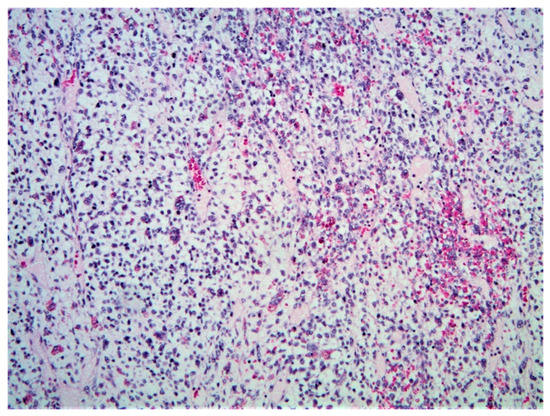

3.2.3. Histopathology